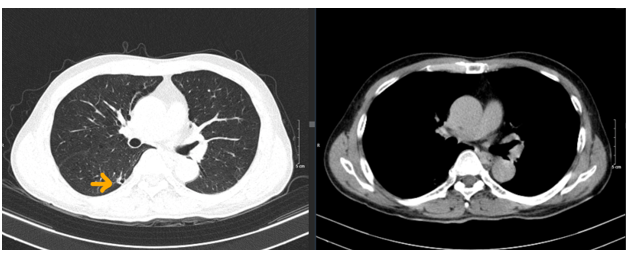

– Chụp cắt lớp vi tính lồng ngực:

Hình 2. Hình ảnh chụp CLVT lồng ngực: nhu mô thùy trên phổi phải có nốt đặc đường kính khoảng 6mm (mũi tên vàng).